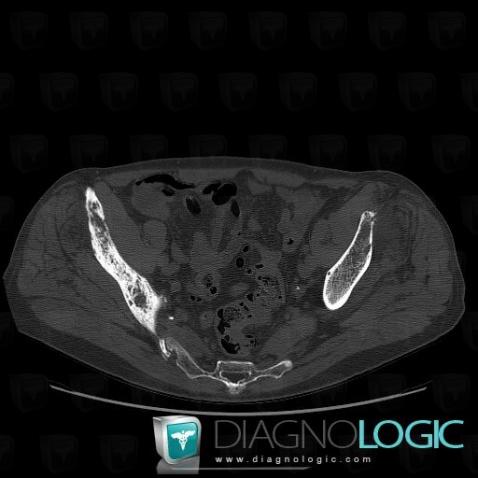

Metastasis, Ilium, CT

Here is the specific information in the key image above:

- Diagnosis Metastasis, Location(s) Ilium, with gamuts Motheaten or permeative lesion, Localised periosteal reaction, Mulltiple osteolysis